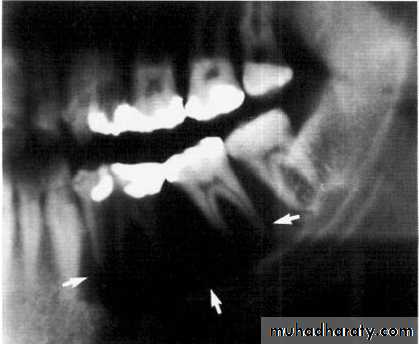

5-year-old boy showing the typical bilateral multilocular lesions of

cherubism affecting the mandible (arrowed).Multiple but separate radiolucent lesions

Histiocytosis-X (Langerhans cell disease):They are three manifestations produce tumour-like lesions in bone, caused by proliferation of Langerhans cells and eosinophilic leucocytes.

Radiographically :

• Multiple radiolucent areas in the interdental & interradicular bone.

• teeth seem to hang in air. Exfoliation of teeth & teeth germ are common, ulceration of overlaying mucosa.

• Multiple radiolucent foci seen in the skull & long bone of the skeleton, lesion in the skull give appearance of geographic map , with skull enlargement .